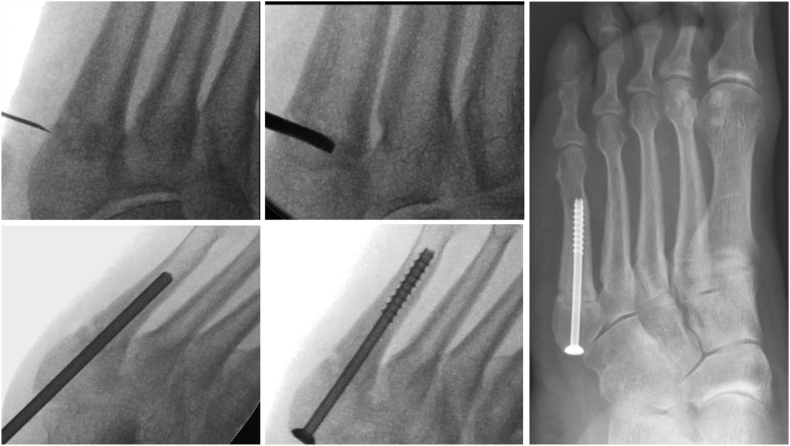

Non-operative management using a non-weightbearing boot has been advocated for stress reactions and undisplaced fractures in non-athletes.2 However, this approach has a higher rate of non-union and a prolonged recovery period.14 In comparison, quicker recovery and union time has been observed with operative management45 which has led some authors to recommend surgical treatment for athletes as standard practice.42 With surgical fixation union rates of 100% have been reported.46 Surgical options include intramedullary screw fixation (Fig. 3) or ORIF using a plate and screw construct with or without bone grafting, however, none have demonstrated superiority.47

Fig. 3.

Nonunion of a zone 3 stress fracture - intraoperative radiographs demonstrating injection of bone marrow, curettage of nonunion site, drilling of sclerotic part of stress fracture and screw fixation with subsequent radiograph at 6 weeks postoperatively. Surgery was performed minimally invasively with a stab incision for curettage and a further stab incision to insert the screw.